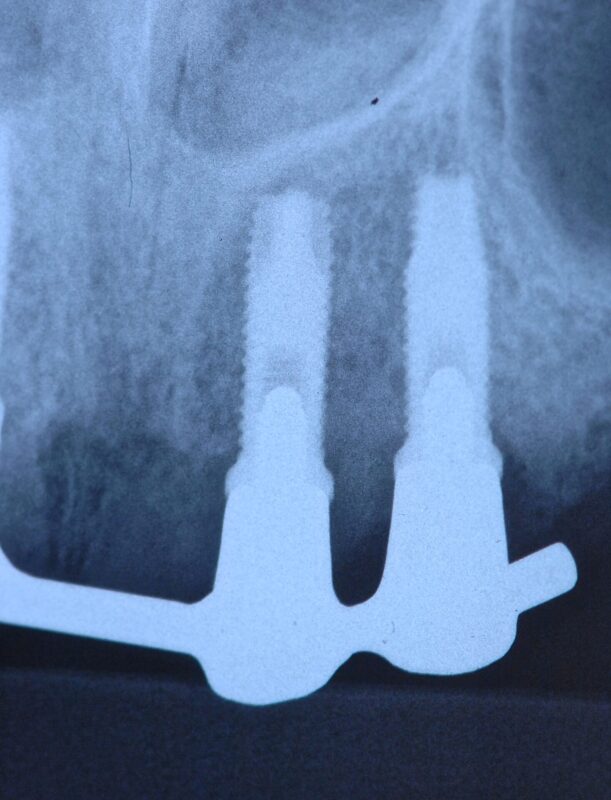

ドルダーバー

ご高齢の方ですが、20年以上前に処置しました。

念の為装着後初めて(20年以上経過)いったん除去したところ(単にネジ止めされているだけですぐ

外れます)2カ所に炎症がありました。

本体には全く問題ありません。

金合金で作製しているため、組織親和性は高いです。

もちろん、インプラント本体にも全く問題ありません。

使用インプラントは3i(アメリカ)。

原因はスクリューが破折していましたので、念の為4本とも全て新しいものと交換しました。

少し空けてチェックに来ていただきましたが、炎症も消失し、全く問題ありません。